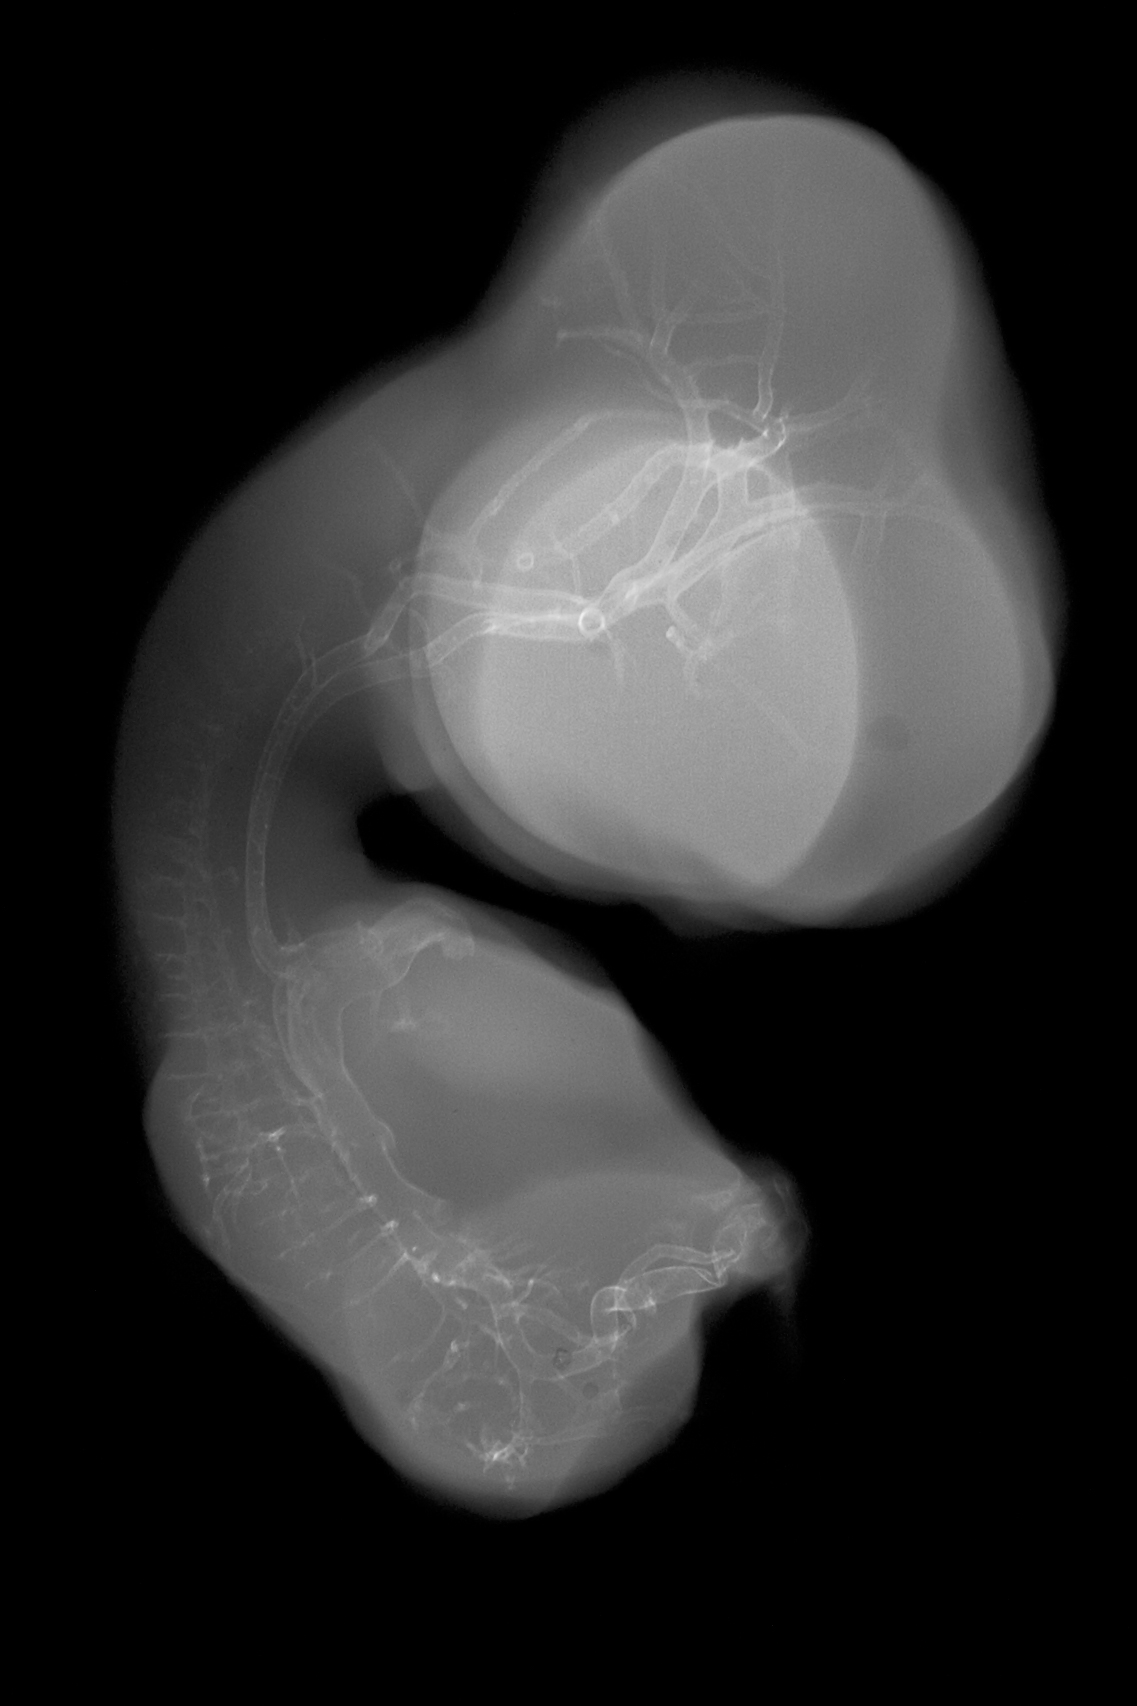

Chick Embryo Microangiography

Hamburger-Hamilton (HH) Stage 30 (approx. 6.5 days)

X-Ray Micrographs